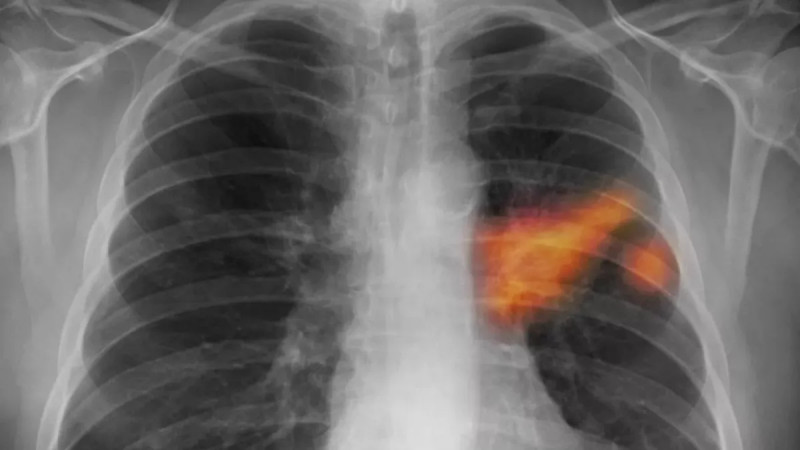

Tomáš Řehoř (57) z Prahy, bývalý kuřák, podstoupil preventivní vyšetření na doporučení lékařky, které odhalilo nezhoubný nádor na plicích, ačkoliv neměl žádné potíže, což dokazuje důležitost včasného screeningu rakoviny plic. #screeningrakoviny #zdraví #prevencetruchu #dobrezpravy

Neměl žádné potíže, přesto mu lékaři našli útvar na plicích. Tomáš Řehoř (57) z Prahy se do programu screeningu rakoviny plic zapojil na doporučení lékařky, a udělal dobře.

Rok co rok je rakovina plic odhalena u více než 6500 pacientů, přičemž pouze u jednoho z deseti je diagnóza stanovena včasné léčitelném stádiu, přičemž preventivní screening pomůže každému druhému vyšetřenému, avšak polovina oslovených na něj nedochází a praktický lékaři tento vyšetřovací program nabízejí jen polovině svých pacientů. #rakovinaplic #screening #prevencetumoru

Každý rok lékaři odhalí rakovinu plic u více než 6500 pacientů, v dobře léčitelném časném stadiu ale jen u desetiny z nich.